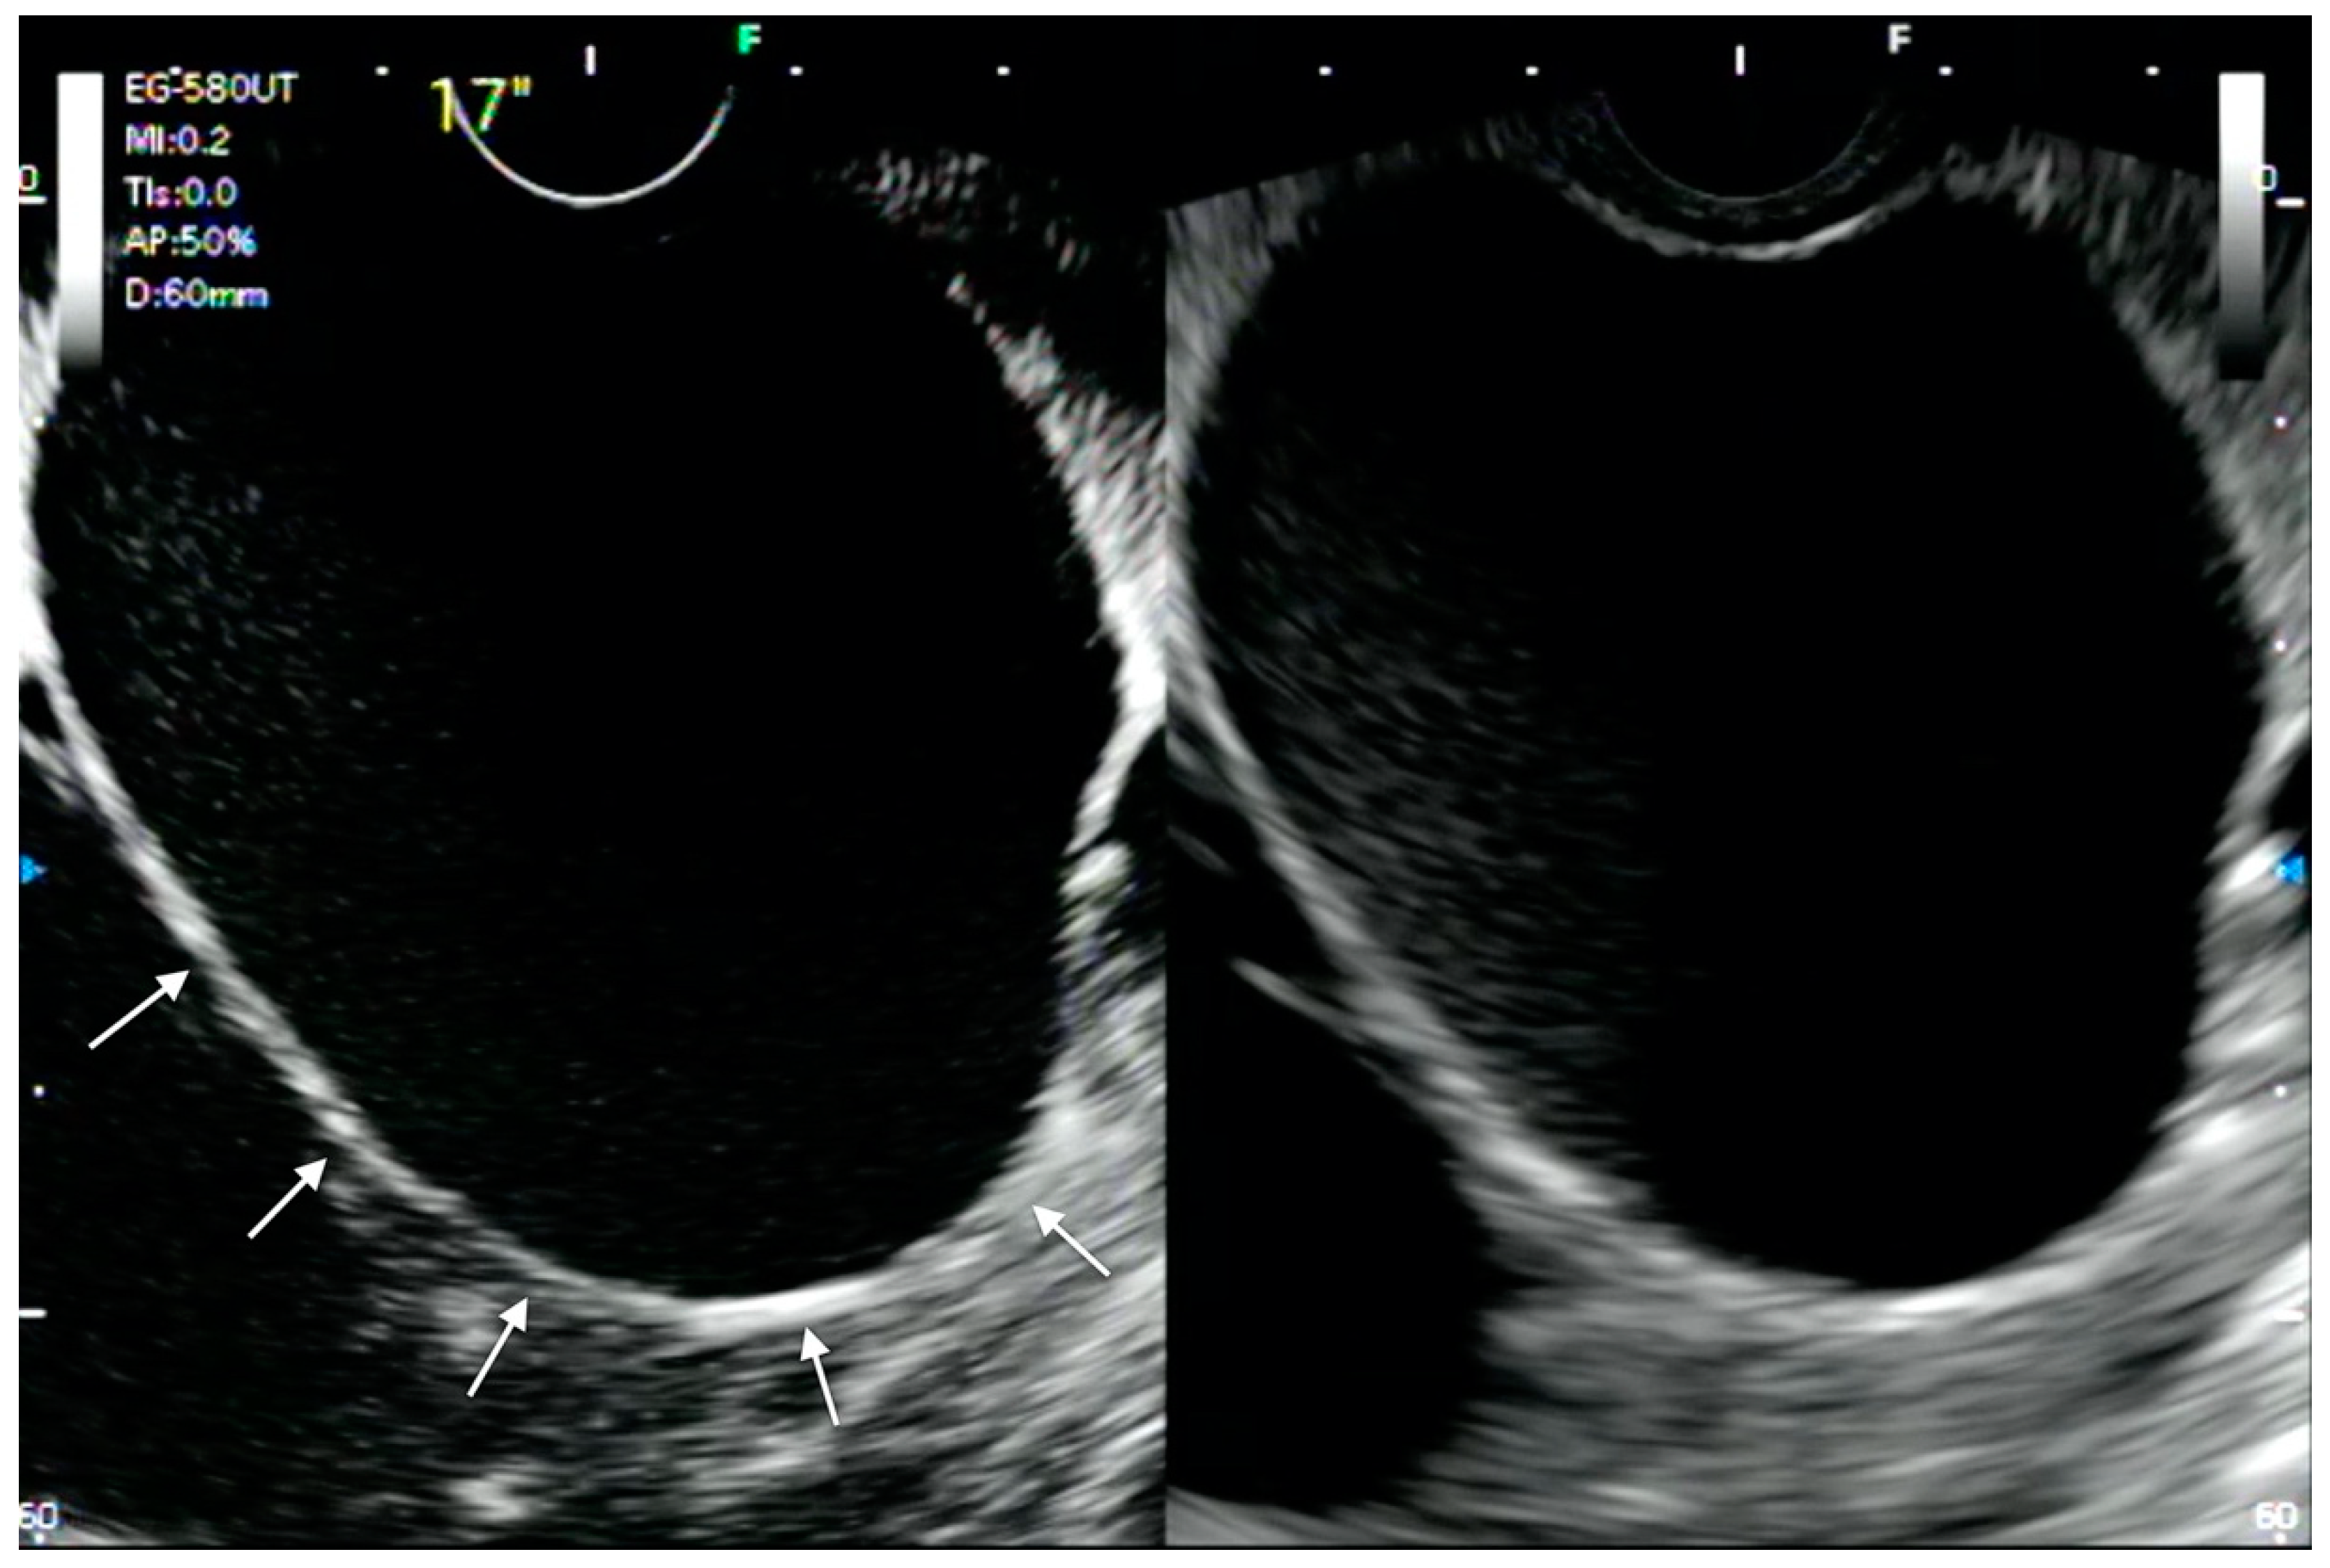

- Minaga, K.; Takenaka, M.; Omoto, S.; Miyata, T.; Kamata, K.; Yamao, K.; Imai, H.; Watanabe, T.; Kitano, M.; Kudo, M. A case of successful transluminal drainage of walled-off necrosis under contrast-enhanced harmonic endoscopic ultrasonography guidance. J. Med Ultrason. 2018, 45, 161–165. [Google Scholar] [CrossRef]